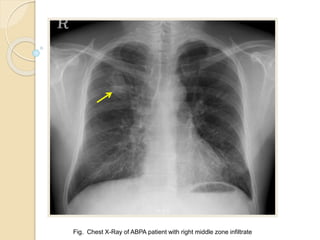

Fig. Chest X-Ray of ABPA patient with right middle zone infiltrate

Radiologic Investigations  Chestradiographic findings  Transient changes ◦ Patchy areas of consolidation ◦ Radiologic infiltrates: toothpaste and gloved finger shadows due to mucoid impaction in dilated bronchi ◦ Collapse: lobar or segmental ◦ Perihilar infiltrates may simulate adenopathy  Permanent changes ◦ Parallel-line shadows representing bronchial widening ◦ Ring-shadows 1–2 cm in diameter representing dilated bronchi en face ◦ Pulmonary fibrosis: fibrotic scarred upper lobes with cavitation CHEST 2009; 135:805–826